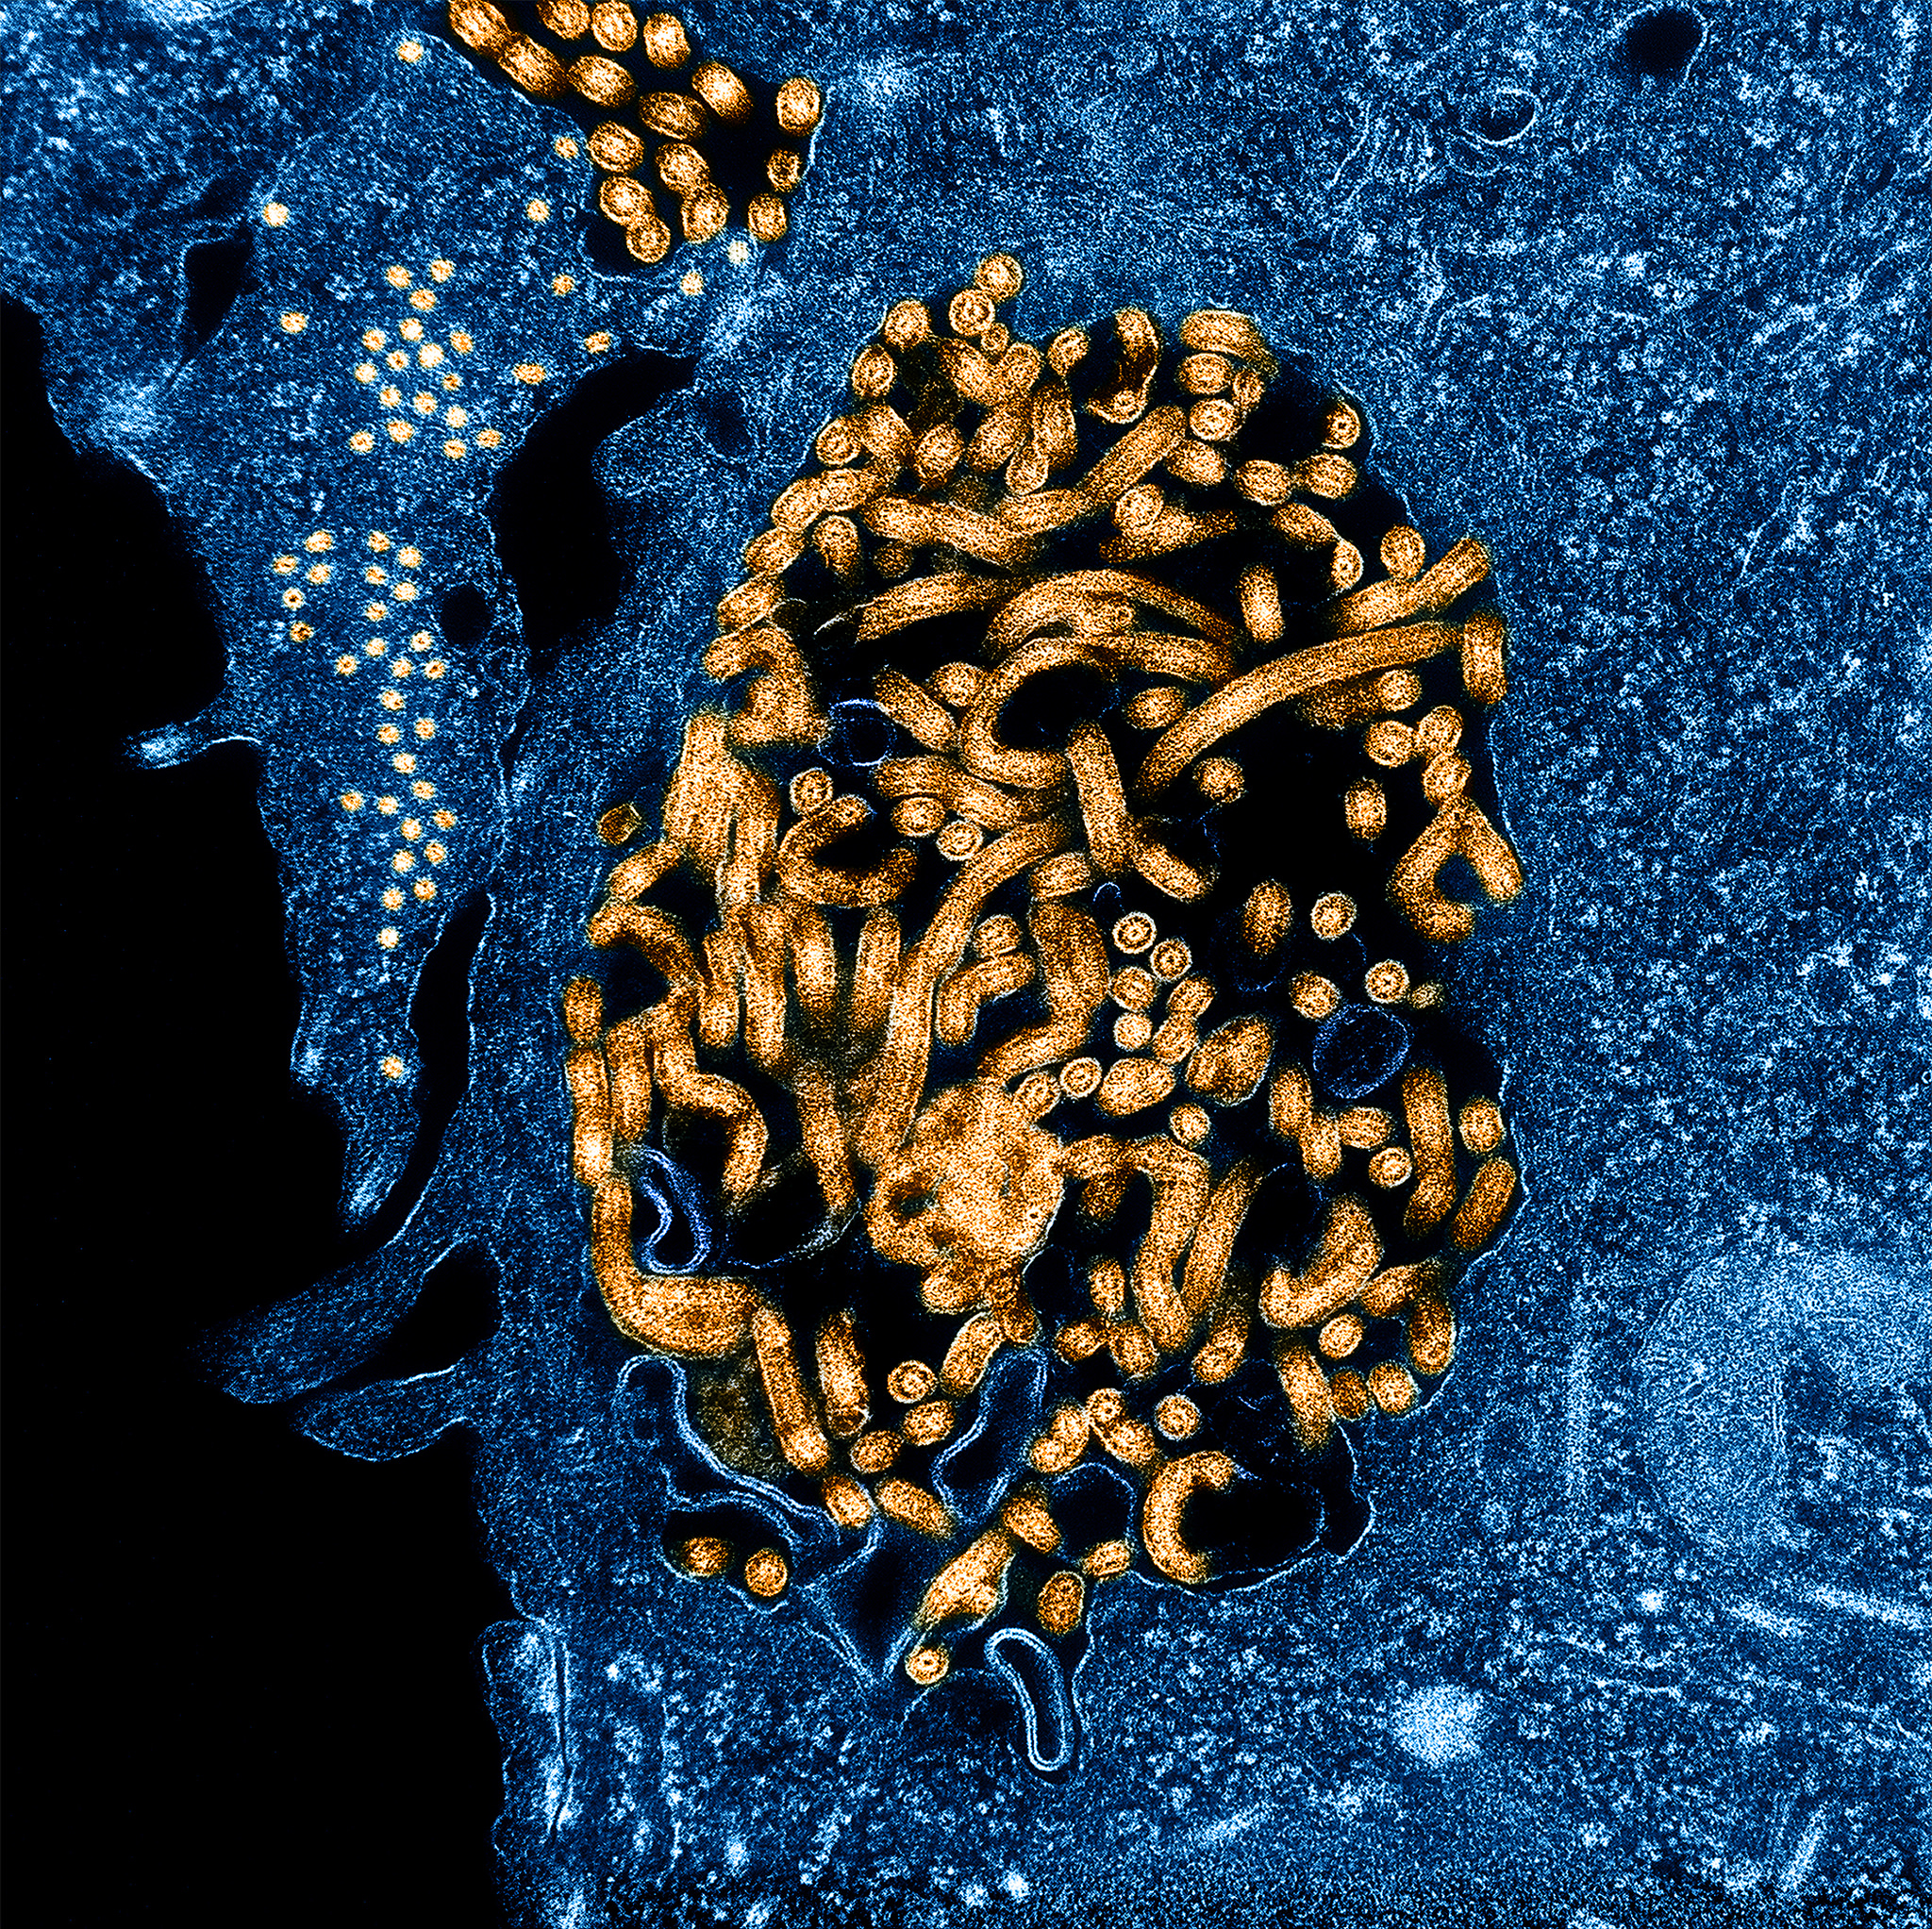

• Daily Dose: WHO took its time declaring Ebola a global health emergency

Daily Dose: WHO took its time declaring Ebola a global health emergency